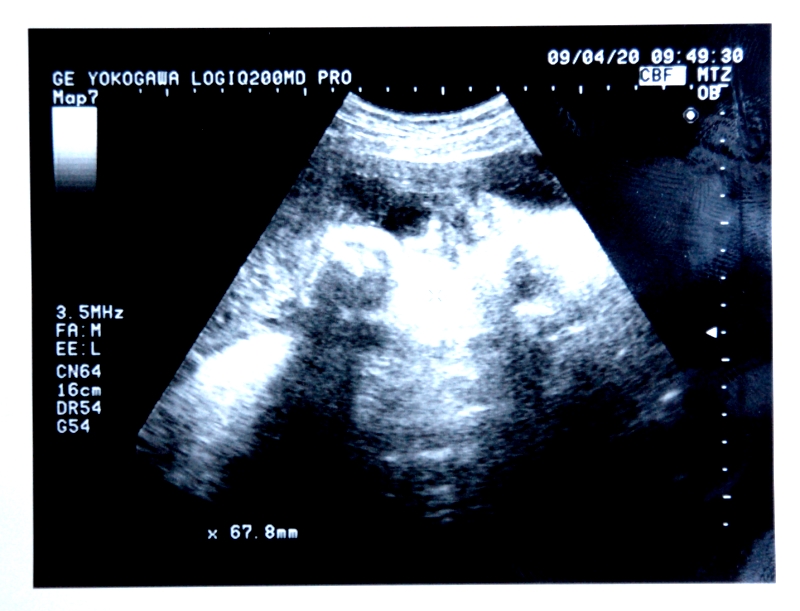

写真は、うちの娘ちゃん(臨月のころ)。当時は、元気に駆けまわっているいまの姿なんて、想像もつきませんでしたネ。しみじみ……。